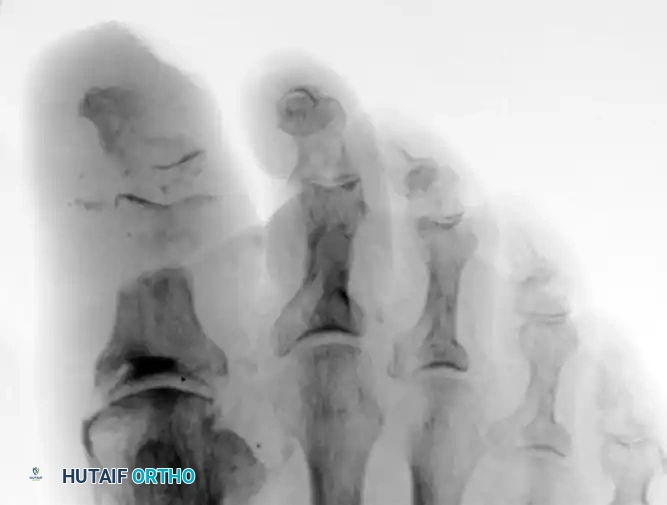

Radiograph demonstrating severe osteomyelitis and bone destruction of the metatarsophalangeal joints, necessitating surgical resection.